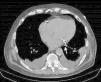

A 61-year-old man, with a history of coronary heart disease and percutaneous coronary intervention, with stents in the right coronary and circumflex arteries, was referred to our center for left atrial appendage (LAA) closure. He had atrial fibrillation with high thromboembolic risk (CHA2DS2VASc=4) and oral anticoagulation was formally contraindicated because of recurrent severe bleeding. Selective angiography of the LAA (Video 1) showed a close relationship between the LAA (Figure 1, asterisk) and the circumflex artery (Figure 1, arrow), well defined by the previously implanted stents. A computed tomography scan performed after a previous episode of diffuse alveolar hemorrhage showed similar findings (Figure 2, arrow). A 22-mm Amplatzer Amulet device was successfully placed, with no residual leak. Intraoperative monitoring by transesophageal echocardiography and post-procedural radioscopy confirmed the close relationship between the device and the circumflex artery (Figures 3 and 4, Videos 2 and 3), which is vital to keep in mind in order to prevent complications during the procedure.